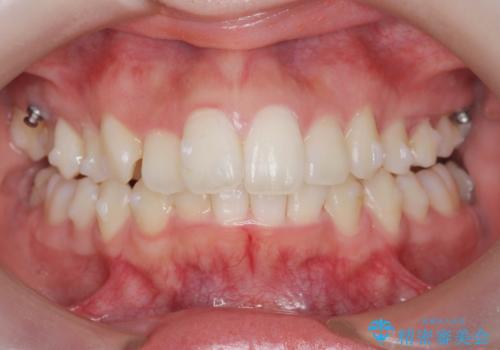

サクソフォン(アルト)の演奏で崩れてしまった歯並び、マウスピース矯正治療

- 高校時代の吹奏楽の部活でサクソフォン(アルト)を担当、「一生懸命練習をしすぎて気づいたら歯並びが悪くなっていた。矯正治療を受けたい!。」

とマウスピース矯正を希望され来院されました。

口腔内の清掃状態の良さに加えて、マウスピースを毎日きっちりと装着し、しっかりと使用していただけたことからワイヤー矯正は行わずにきれいに歯並びを治すことができました。

途中顎位が変わり、マイクロインプラントを併用した上顎臼歯の遠心移動が必要となったため治療が長期化しました。